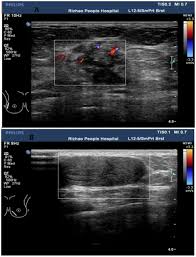

Ultrasound imaging allows better evaluation of the status of the axillary lymph nodes in patients with ibc, an important step in determining extent of disease prior to initiation of chemotherapy. However, a dark spot on your ultrasound doesn't mean that you. It is the most common cause of cancer death in women. in 2005 alone, 519 000 deaths were recorded due to breast cancer. this means that one in every 100 deaths worldwide and almost one in every 15 cancer deaths were due to breast cancer. On ultrasound, a breast cancer tumor is often seen as hypoechoic, has irregular borders, and may appear spiculated. In the table the differences in ultrasound appearances are listed.

Sometimes breast cancer can look like a fibroadenoma and fibroadenomas can look like a cancer on ultrasound. Ultrasound imaging allows better evaluation of the status of the axillary lymph nodes in patients with ibc, an important step in determining extent of disease prior to initiation of chemotherapy. Any area that does not look like normal tissue is a possible cause for concern. However, a dark spot on your ultrasound doesn't mean that you. If you're younger than 25.

This breast cancer ultrasound image shows changes related to breast cancer that are not seen as microcalcifications or a mass or lump. Any area that does not look like normal tissue is a possible cause for concern. If your breast tissue is too dense for a mammogram. Ultrasound imaging allows better evaluation of the status of the axillary lymph nodes in patients with ibc, an important step in determining extent of disease prior to initiation of chemotherapy. If a solid lump shows on the scan you might need to have. It is the most common cause of cancer death in women. in 2005 alone, 519 000 deaths were recorded due to breast cancer. this means that one in every 100 deaths worldwide and almost one in every 15 cancer deaths were due to breast cancer. With ultrasound, the radiologist will probably be trying to get a sense of the internal texture of the breast lesion and surrounding area. Physical examination and mammogram can be more accurate in some settings. If there are calcifications within the nodular dcis, one may be able to see these on ultrasound as white flecks. The images that a breast ultrasound produces are in black and white. A diagnostic mammogram is used to check for breast cancer when there is a sign or symptom of disease. A breast ultrasound is most often done to find out if a problem found by a mammogram or physical exam of the breast may be a cyst filled with fluid or a solid tumor. To look more closely at a.

Staging Of Breast Cancer With Ultrasound Sciencedirect from ars.els-cdn.com Ultrasound characterization of breast masses. indian journal of radiology and imaging. Other names for this test: Ultrasound is only one means of evaluation of the breast. Tumors are likely to be smaller when doctors detect them early, which can. Breast cancer is among the most common causes of cancer deaths today, coming fifth after lung, stomach, liver and colon cancers. Any area that does not look like normal tissue is a possible cause for concern. In the table the differences in ultrasound appearances are listed. Overall, 57 (20.8%) of the 274 women had cancer in the axillary lymph nodes.